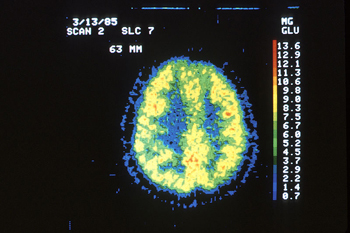

PET scan of a normal brain.